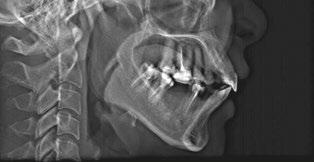

Patient S.T., age 32, presented in the hope of creating a radiant smile and a functional bite. She had been dealing with dental problems all her life. Her X-rays exhibited multiple direct restorations as well as endodontic treatment. Due to the loss of her molars, her teeth had shifted considerably over the years. Her dentist recommended she see us to create a pleasing smile and to rehabilitate her occlusion for future prosthetic treatment (Figure 8).

The patient’s occlusion was super CL I on the left and CL II on the right. Both arches showed slight constriction with lower anterior crowding. Her smile arc was canted, and both midlines were shifted in opposite directions. On cephalometric

analysis, her ANB was 5.84, and IMPA was 102.64, both representative of skeletal Class II with incisor proclination. There were two long-standing extraction sites into which the UR6 and UL6 (partial) had supraerupted. Her thin gingival mucosa posed a challenge in keeping the roots in the bone, so treatment had to be planned correctly and executed gradually to maintain her gingival architecture.